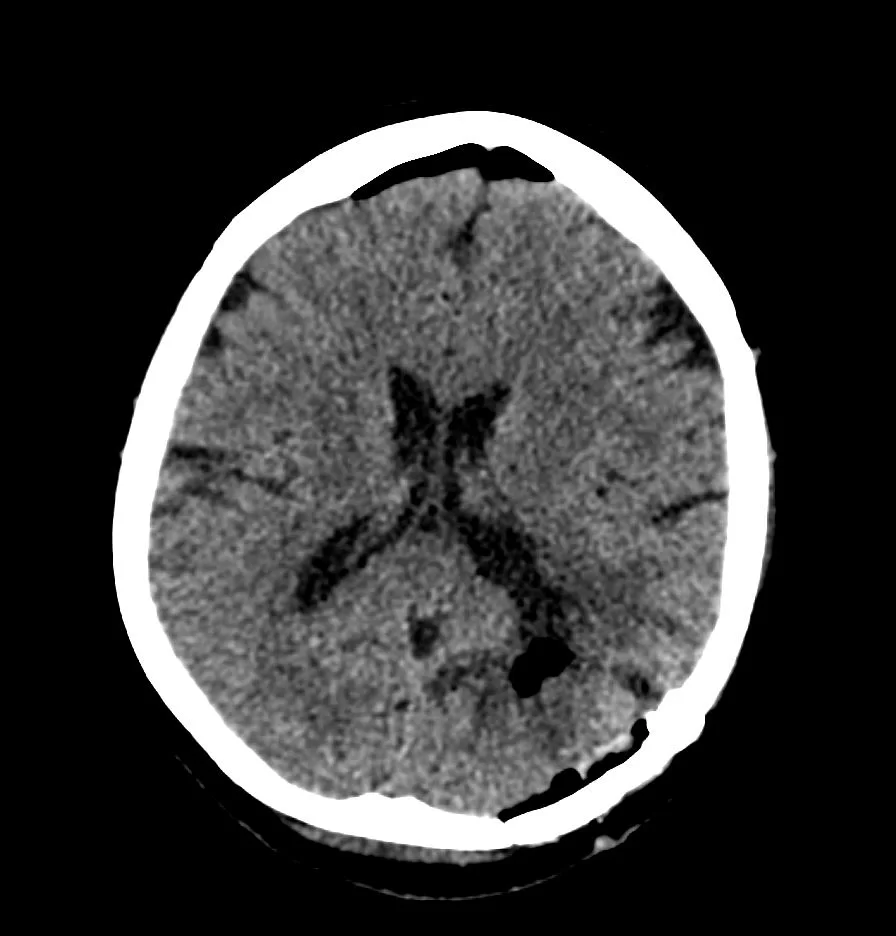

Η μετεγχειρητική αξονική τομογραφία εγκεφάλου δείχνει πλήρη αφαίρεση της βλάβης. Η ιστολογική εξέταση ανέδειξε μηνιγγίωμα WHO I.